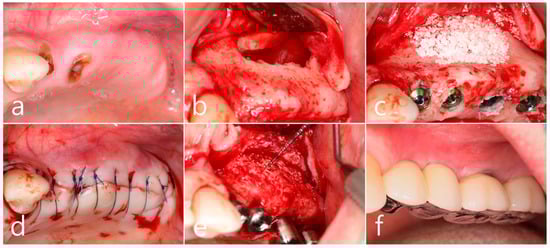

In the preoperative clinical picture of the maxillary left posterior region, root rest of #24 and #25 teeth were observed (Figure 2a). Under local anesthesia, the buccal mucoperiosteal flap was reflected, a lateral sinus window was prepared, and the sinus floor was elevated using a sinus elevation instrument (Genoss, Suwon, Republic of Korea). The sinus membrane was not perforated (Figure 2b). Approximately 1.5 cc of Osteon II (Genoss, Suwon, Republic of Korea) was filled in the elevated sinus cavity, and 4 implants (3.8 × 12, 4.3 × 10 Implantium, Dentium, Suwon, Republic of Korea) were placed subcrestally. The thickness of the buccal bone in the ridge crest area was sufficiently maintained (Figure 2c). The lateral window site was covered with a resorbable collagen membrane (Genoss, Suwon, Republic of Korea), and the mucoperiosteal flap was then closed with 4-0 nylon (Figure 2d). Healing was uneventful. Uncovering was performed 6 months after surgery. Resistance was felt when penetrated with a periodontal probe. It was confirmed that bone regeneration was successful. The cover screw was removed, and the healing abutment was inserted. The mucoperiosteal flap was closed (Figure 2e). After 2 months, the final prosthesis was delivered (Figure 2f).

Figure 2. (a) Preoperative clinical photograph of the maxillary left posterior region showed root rest of #24 and #25 teeth; (b) After the mucoperiosteal flap was reflected, sinus floor elevation was performed. The sinus membrane was not perforated; (c) A bone graft substitute was filled in the elevated sinus cavity, and 4 implants were placed subcrestally. The thickness of the buccal bone was sufficiently maintained; (d) The lateral window site was covered with a resorbable collagen membrane and then closed with 4-0 nylon; (e) Uncovering was performed 6 months after surgery. Resistance was felt when penetrated with a periodontal probe; (f) Prosthesis was delivered 2 months later.